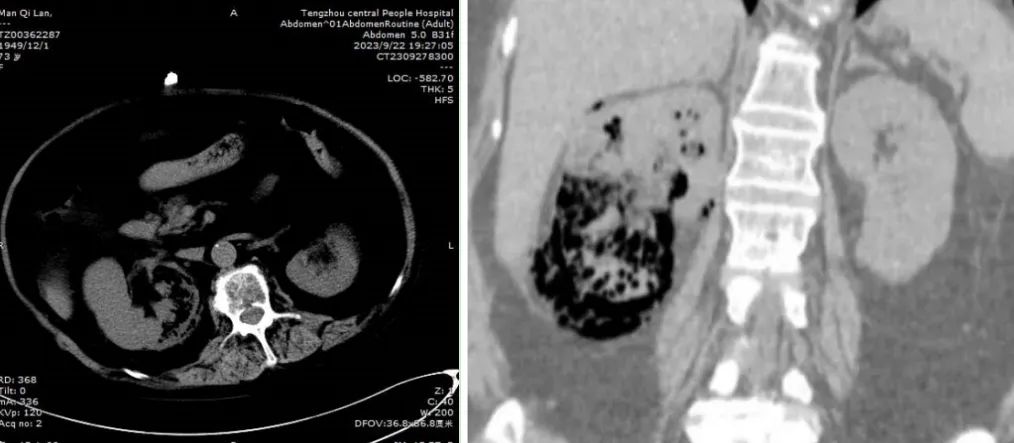

满阿姨转入泌尿外二科后,单锋芝副主任医师组织科室讨论,认为患者有长期服用糖皮质激素,免疫力下降等诱发本病的危险因素,经CT检查,诊断“气肿性肾盂肾炎”成立,明确治疗方案为抗菌素+内置输尿管支架引流+肾穿刺造瘘治疗。尽管方案制定好了,但具体治疗过程却出现了波折。首先患者的输尿管支架管未能进入肾盂,差1-2cm,不能充分引流肾盂压力。其次,肾脏内及肾周的气体在超声影像下定位困难,在超声介入薛涵文副主任医师的主导下,成功在肾上极经皮置入肾造瘘管一根。但10天后,患者的病情并没有明显的改善,反而出现了肾功能不全,电解质紊乱的情况。单逢芝副主任医师立即组织进行多学科会诊,CT室张兆明主任对影像诊断进行分析,指出感染灶多发的特点;感染科杨列永主任提出重点在于局部感染灶的处理,调整抗菌素,必要时肾脏切除的建议;风湿免疫科指出,患者的肾上腺皮质功能受抑制,节律紊乱,不能停止服用激素,继续药物补充。多学科诊疗后,医护人员和患者家属进行充分沟通,在彩超室再次为患者进行肾脏下极的穿刺造瘘术,并在护理人员及家属的大力配合下保持造瘘管的引流通畅,同时纠正电解质紊乱,改善患者的营养状况,患者的病情逐步好转。1个多月后,在全科医护人员的精心治疗、护理下,患者逐步拔除肾造瘘管,取出体内的输尿管支架管,停用抗菌素,观察3~5天病情平稳,痊愈出院。“医德高尚、医术精湛”,患者及家属对治疗非常满意,特赠送锦旗一面。满阿姨激动地说:“是你们救了我一命,太感谢你们了!”气肿性肾盂肾炎根据CT表现,可以分成严重程度不同的四种类型,不同的类型恢复时间不同,采用的治疗策略侧重点也不相同。此例患者的成功治愈,锻炼了泌尿外二科医疗、护理队伍的整体技能水平及综合素养,体现了我院多学科诊疗水平再上新台阶。